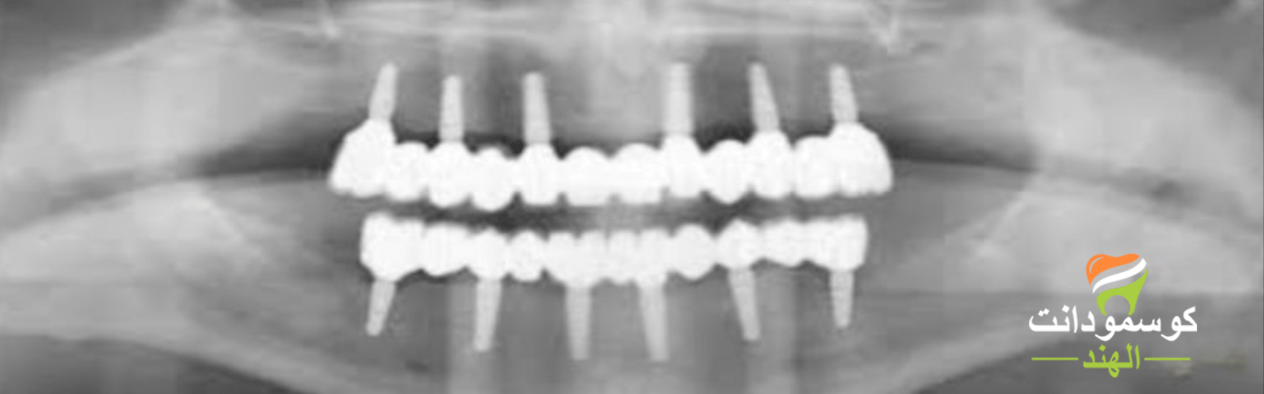

تعتمد زراعة الأسنان “الكل على ستة”على ست غرسات أسنان تشمل الفكين العلوي والسفلي. تُزرع الغرسات الست في الفك واحدة تلو الأخرى، مما يُشكل دعامات لتثبيت الجسور والتيجان، حسب حالة المريض

الكل على ستة تستخدم ستة زرعات من التيتانيوم في الفكين الفك العلوي والفك السفلي لتثبيت طقم الأسنان في مكانه. توفر هذه الطريقة أفضل مستويات الراحة ومتانة إضافية